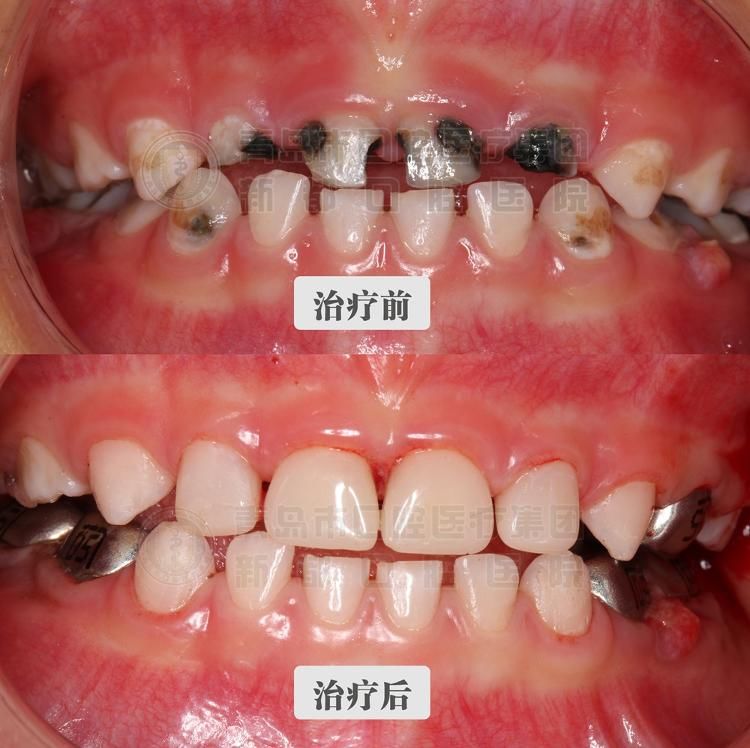

舒适|3岁男童“一觉”醒来满口烂牙变白牙 无痛舒适化口腔治疗让孩子轻松看好牙

大众网·海报新闻采访人员 赵尊 青岛报道随着人们口腔卫生保健意识的增强和生活水平的提高,儿童口腔疾病越来越引起家长的重视,然而震耳欲聋的号啕哭声、在诊疗椅上扭动抗拒大喊“我不要”,相信是许多家长带孩子看牙医时最无可奈何的一刻。12月17日,佳佳(化名)父母带着三岁半的佳佳从莱西辗转一百多公里来到青岛市口腔医疗集团新都口腔医院进行治疗,经过三个半小时,佳佳15颗龋齿修复治疗顺利完成。该院开展的无痛舒适化口腔治疗让患儿在全麻下一次性治疗所有患牙,大大缩短了治疗周期。“只要宝宝睡一觉,醒来我们还他一口健康的牙齿。”青岛市口腔医院儿牙专家赵霞主任说。

睡一觉醒来 15颗龋齿全“消失”佳佳平时没有良好的口腔卫生习惯,一年前有颗牙齿开始发黑,变坏,家长当时也没太在意。可最近两个月牙齿变坏的速度加快,牙龈出现鼓包流脓的情况,脸肿的厉害,坏牙甚至要多于健康的牙齿。佳佳因为牙齿的疼痛寝食难安,家长看了之后也心疼不已。佳佳的母亲带着他去了当地牙科诊所检查,根据检查,佳佳共有20颗牙齿,其中15颗已经变坏,需要治疗。“当时也去了好几个地方,由于牙齿坏的太多,一颗颗治疗的话,孩子很害怕也不配合,所以不太现实。”佳佳母亲说。后来经过打听、比较,最后选择了青岛市口腔医疗集团新都口腔医院,采用无痛舒适化口腔治疗。

【 舒适|3岁男童“一觉”醒来满口烂牙变白牙 无痛舒适化口腔治疗让孩子轻松看好牙】据赵霞介绍,以往的儿童口腔疾病治疗过程,一次最多治疗1~2颗坏牙,而且有些牙齿可能要进行多次治疗。倘若全口都是蛀牙,那么治疗的周期就会大大增长,会长达半年或者半年以上。在龋齿治疗过程中,最大的难点在于孩子的配合度。一般情况下,年龄较小的儿童,较难配合医生进行复杂的口腔治疗。以往的捆绑束缚式治疗不仅会使孩子哭闹挣扎、逃避治疗,治疗效果也是差强人意,严重时会导致孩子患上“牙科恐惧症”。“而现在针对于儿童口腔出现的这种全麻下舒适化治疗就具有非常明显的优势。”赵霞说到,“相比于以往的治疗手段,在全麻状态下,医生能够提高治疗的质量,可以一次性进行全口换牙,省去了家长和患儿的多次奔波,同时患儿不会产生任何的痛苦的记忆,孩子们睡一觉醒来就有了一口健康的小白牙”。